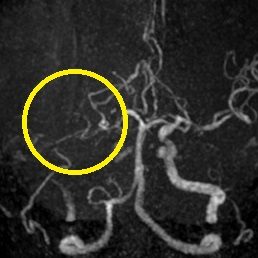

超急性期脳梗塞に対する血栓溶解療法(t-PA治療)

ろれつ困難と左半身重度麻痺のため当院に救急搬送となった患者様に対し、発症2時間30分でt-PAの投与を開始。t-PA開始1時間半後に左麻痺とろれつ困難は回復し始め、翌日には症状は消失。t-PA後のMRA検査で閉塞血管の完全再開通を認め、発症から2週間後に神経症状なく退院。

(来院時MRA検査画像)